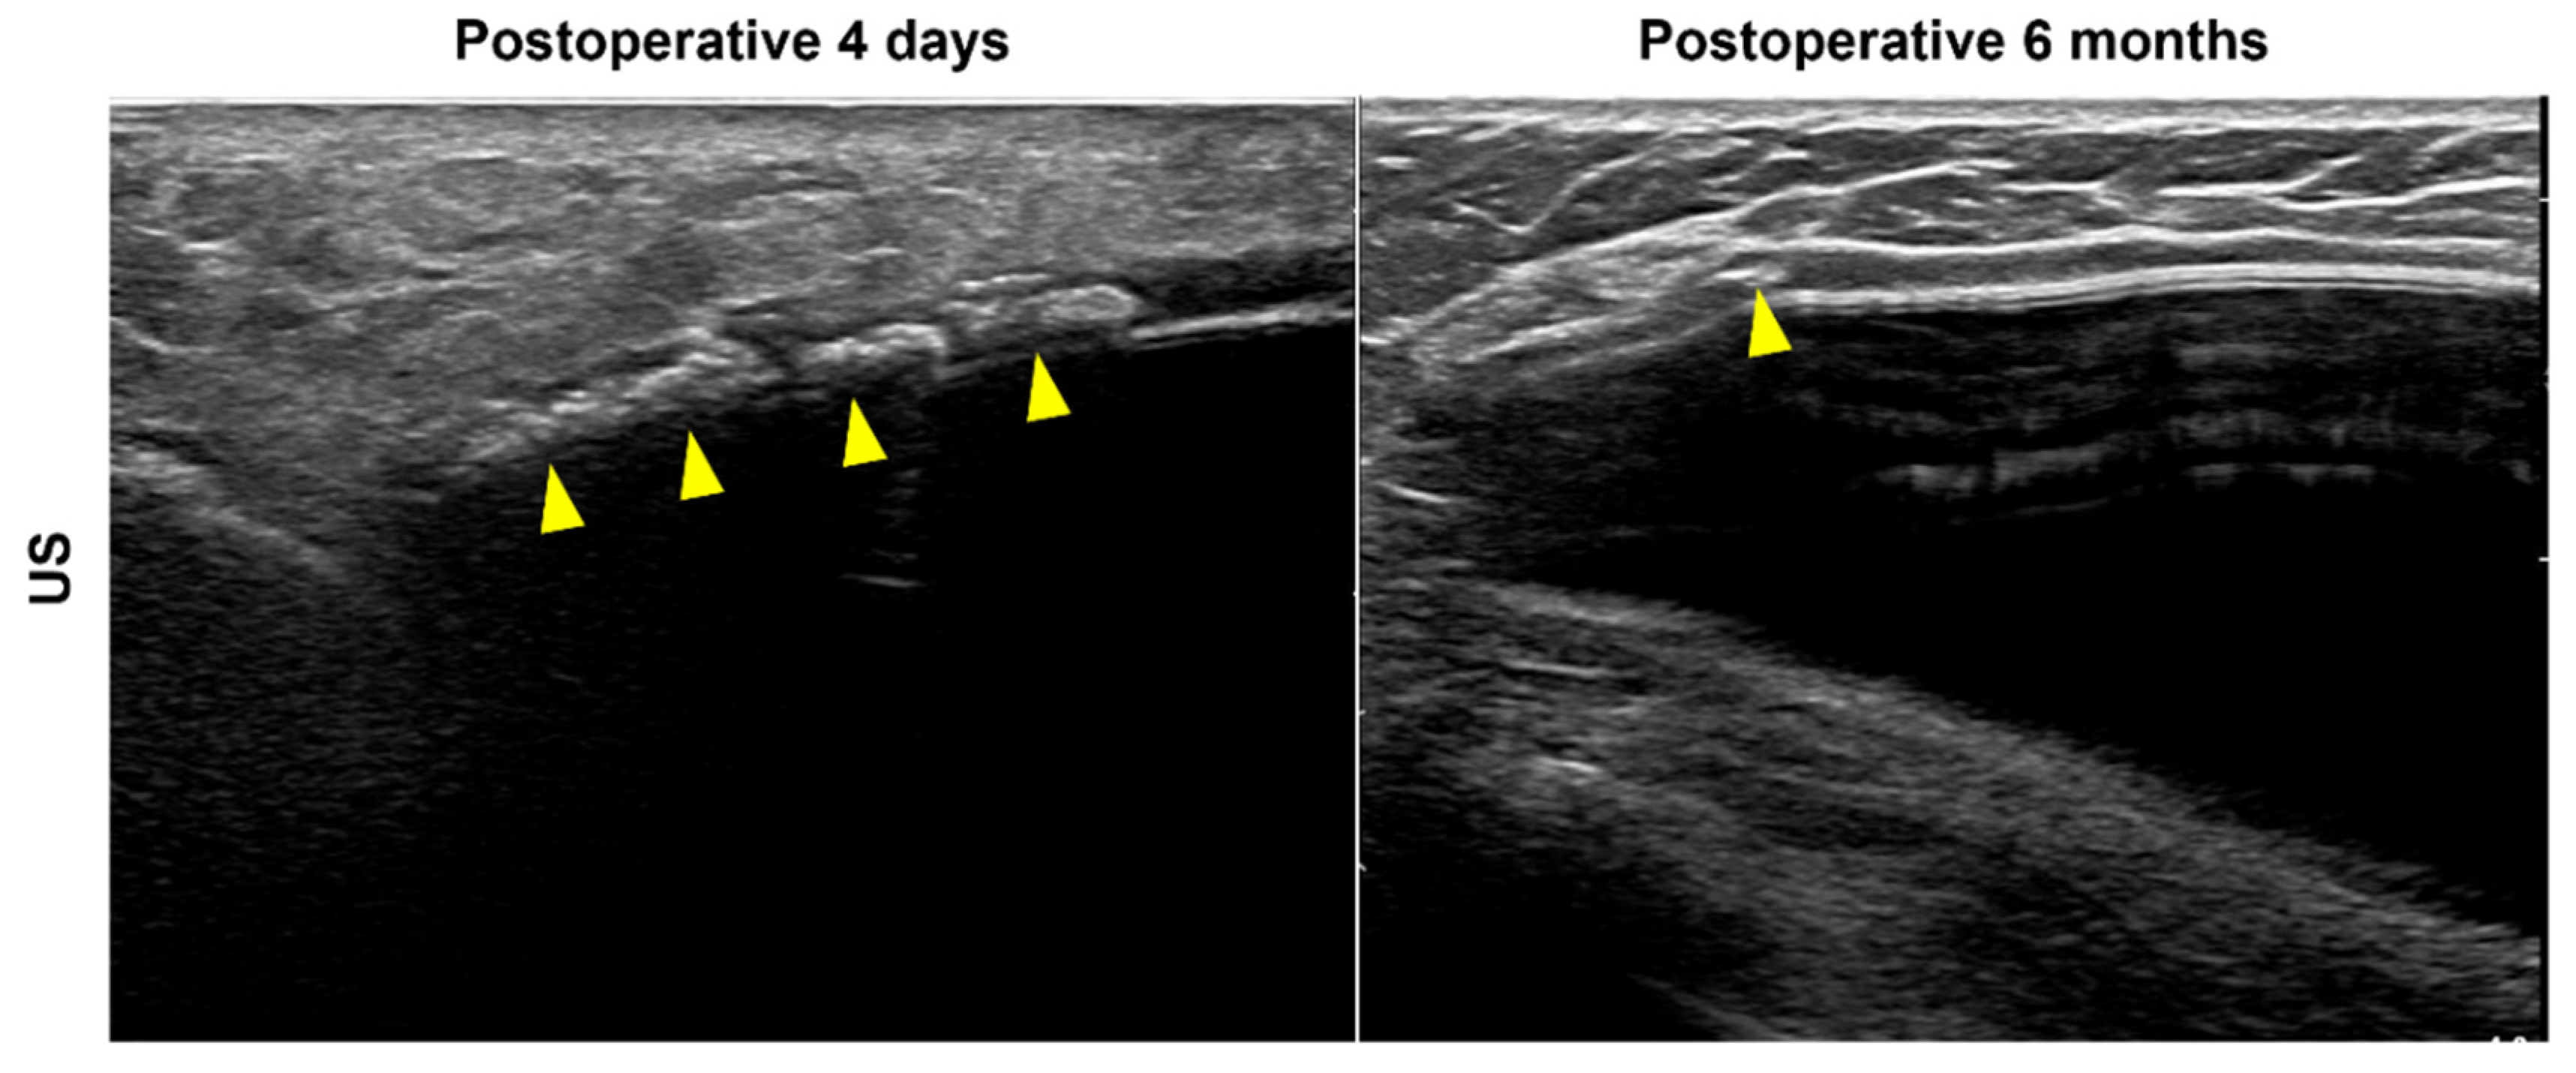

In this study, we hypothesized a hyperechoic spot due to calcification inside the ADM for type 3 cases, but calcification was not histologically observed. Instead, multiple empty spaces were visible inside the ADM, perhaps because air was trapped in the empty spaces, appearing as bright hyperechoic dots in the US image. These empty spaces may be the result of skin appendage necrosis. Another possibility is the disappearance of fluid or fat during the process of creating the dermal matrix, where a cyst or fat necrosis in the donor tissue once was, entrapping air. For example, these bright, hyperechoic dots were diffusely observed in the ADM of a patient who received US imaging immediately after surgery (i.e., at 4 days postoperatively) (Figure 3). In the 6-month follow-up US examination, the number of bright echogenic spots in the ADM was considerably reduced (Figure 3).

Figure 3.

Acellular dermal matrix (ADM) ultrasound (US) findings in implant-based breast reconstruction. US imaging immediately after surgery (postoperative day 4) shows bright, hyperechoic dots diffusely visible in the ADM (arrowheads, left). After six months, the number of bright echogenic spots in the ADM reduced considerably (arrowhead, right).